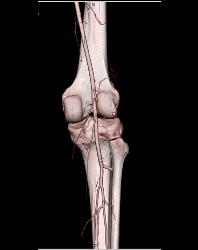

Patent Popliteal Artery and Trifurcation